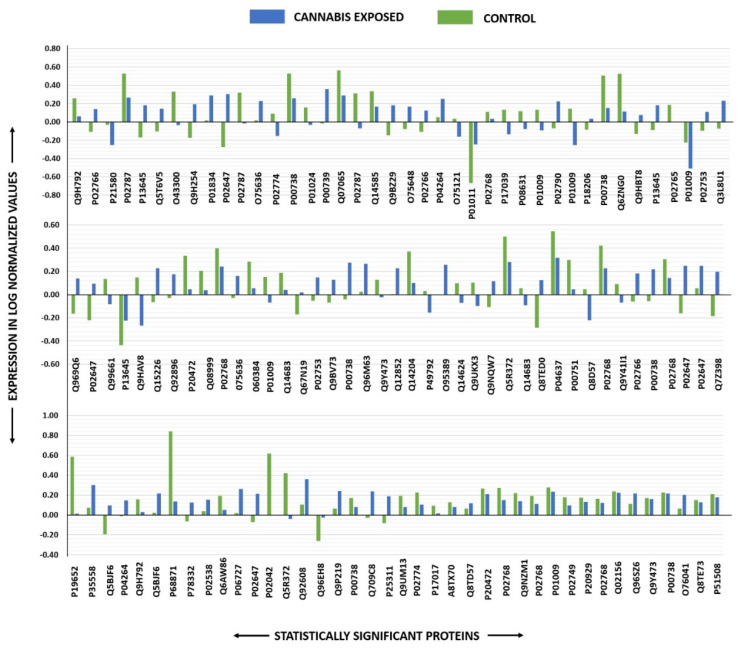

Peptide mass fingerprints (PMFs) identified 121 out of 156 protein spots that were excised from preparative gel, MALDI-TOF. MS found 85 spots to be unique protein sequences. These sequences were matched to the SWISS-PROT database by Mascot search engine with high confidence scores (Table 2, Supplementary Table S2). The sequence coverage ranged from 4% to 85%. In few cases, the same protein variants were found at several locations on the gel (Table 2, Figure 2). Among the 121 proteins identified, 55 were upregulated and 66 were downregulated in the samples of CUD patients compared with that in the control subjects (Table 2, Figure 3). The significantly upregulated proteins included Apolipoprotein A-I (up 3.8-fold, p = 0.01), Alpha-1-antichymotrypsin (up 2.7-fold, p = 0.02), U3 small nucleolar RNA-associated protein 15 homolog (up 2.6-fold, p = 0.03), Zinc finger protein 550 (up 2.4-fold, p = 0.04), Haptoglobin-related protein (up 2.4-fold, p = 0.01), Spectrin beta chain, non-erythrocytic 4 (up 2.3-fold, p = 0.01), Keratin, type I cytoskeletal 10 (up 2.2-fold, p = 0.007), Dedicator of cytokinesis protein 9 (up 2.1-fold, p = 0.02), Haptoglobin (up 2.4-fold, p = 0.01), and Serine/threonine-protein phosphatase 2A regulatory subunit B’’ subunit gamma (up 2.0 fold, p = 0.05); a complete list is provided in Table 2. By contrast, the significantly downregulated proteins in CUD subjects included Hemoglobin subunit beta (down 5.0-fold, p = 0.05), Alpha-1-acid glycoprotein 2 (down 3.7-fold, p = 0.04), Rab GTPase-activating protein 1-like (down 2.9-fold, p = 0.02), and Ubiquitin domain-containing protein 1 (down 2.6-fold, p = 0.04) (Table 2, Supplementary Table S2). Among identified proteins: Inactive tyrosine protein kinase PEAK1, Transthyretin; Serotransferrin; Keratin, type I cytoskeletal 10; Apolipoprotein A-I; Ficolin-3; Vitamin D-binding protein; Haptoglobin; Keratin, type II cytoskeletal 1; Albumin; Alpha-1-antitrypsin; Retinol-binding protein 4, Outer dense fiber protein 2; Dynein heavy chain 3, axonemal; Parvalbumin alpha; Rab GTPase-activating protein 1-like; Structural maintenance of chromosomes protein 1A and Zinc finger protein 175 were found in ≥1 spot on the gels, which could be explained by post-translational modifications, cleavage by enzymes, or different protein species presence.